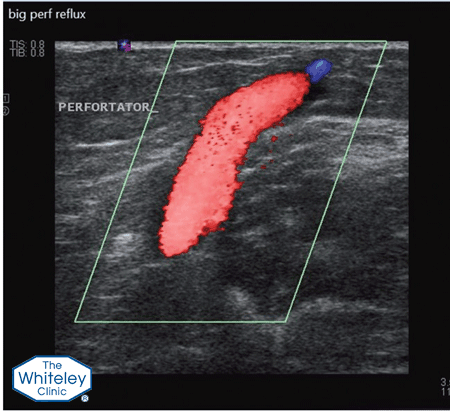

Incompetent perforating veins are only 2 or 3 mm across and can occur virtually anywhere on the leg. As such they cannot be seen on the surface and, even using the top venous duplex ultrasound machines, are very difficult to spot. The Whiteley Clinic vascular scientists are trained to look for these and to mark them precisely. Incompetent perforating veins are often ignored by doctors who do their own scans and who do not find them.